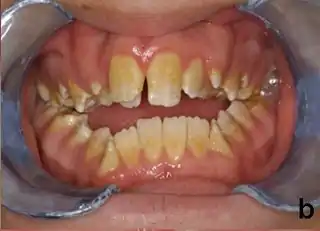

Las personas afectadas con amelogenesis imperfecta tienen dientes con color anormal: amarillo, marrón o gris. Los dientes tienen un mayor riesgo de sufrir cavidades dentales y son hipersensitivos a los cambios de temperatura. Este desorden puede afectar cualquier número de dientes.

Las mutaciones en algunos de estos genes alteran la estructura de estas proteínas o incluso impiden a los genes producir por completo las proteínas. Como resultado el esmalte dental es anormalmente fino o suave y puede tener un color amarillo o marrón. Los dientes con esmalte defectuoso son débiles y fácilmente dañados.